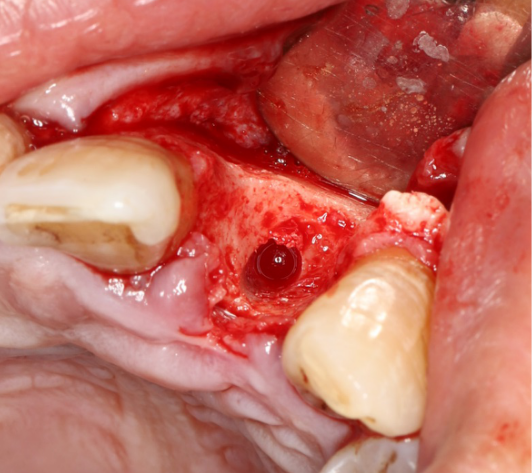

使用12#镰形刀片沿21、22、23做龈沟内切口,于24近中做垂直附加切口。

翻开全厚粘骨膜瓣,暴露22颊侧牙槽骨,微创拔除22。

搔刮22拔牙创,暴露22牙槽骨表面,开放骨髓腔。

旋入种植体,初期稳定性为 30N。

直接上愈合基台。